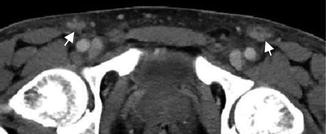

Kaposi sarcoma in a 35-year-old man (endemic type). Computed tomography after iodinated-contrast injection shows an enhancing bilateral inguinal lymphadenopathy (arrows)